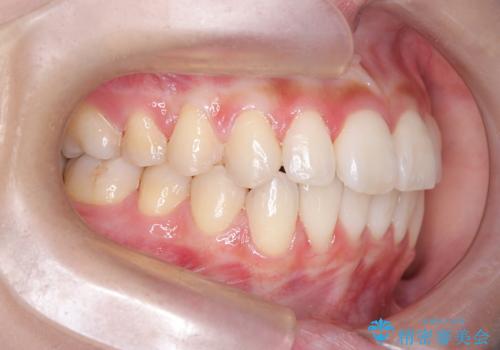

反対咬合を治したい。インビザライン

- 前歯の反対咬合を治したいことを主訴に来院されました。

インビザラインにて臼歯の遠心移動を行いながら、スペースを作り反対咬合を改善することができました。